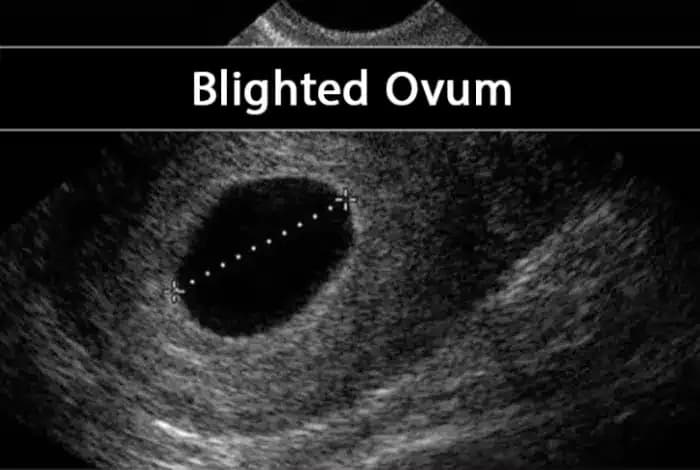

Blighted Ovum After PGT-A Embryo Transfer: What Intended Parents Should Know

Discover why a blighted ovum can occur even after a PGT-A tested embryo transfer. Learn the causes, medical options, and how intended parents can move forward with hope.